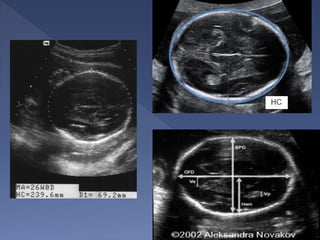

 Bi-parietal diameter

 Head circumference

Landmarks :

 Midline Falx

cerebri

 Cavum septum

pellucidum

 Thalami

symmetrically

positioned on

either side of the

falx

 Lateral ventricle

 The diameter between the 2 sides of the

head

 This is measured after 13 weeks.

 Dating using the BPD should be done as

early as is feasible.

 Different babies of the same weight can

have different head size, therefore dating in

the later part of pregnancy is generally

considered unreliable

 The BPD remains the standard against

which other parameters of gestational age

assessment are compared

 A wrong measurement plane can produce

errors up to 20mm !

 The measurement is taken from the

outer edge of the near cranium to the

inner edge of the far cranium.

 a middle-to-middle measurement is

also acceptable.

 The BPD can be smaller (and sometimes

much smaller than is expected) in

fetuses with flatter heads(check the

head circumference)

Landmarks:

 Same as BPD

 On the outer

margin of the bony

skull

 Independent of

skull shape

 More indicative of

gestational age